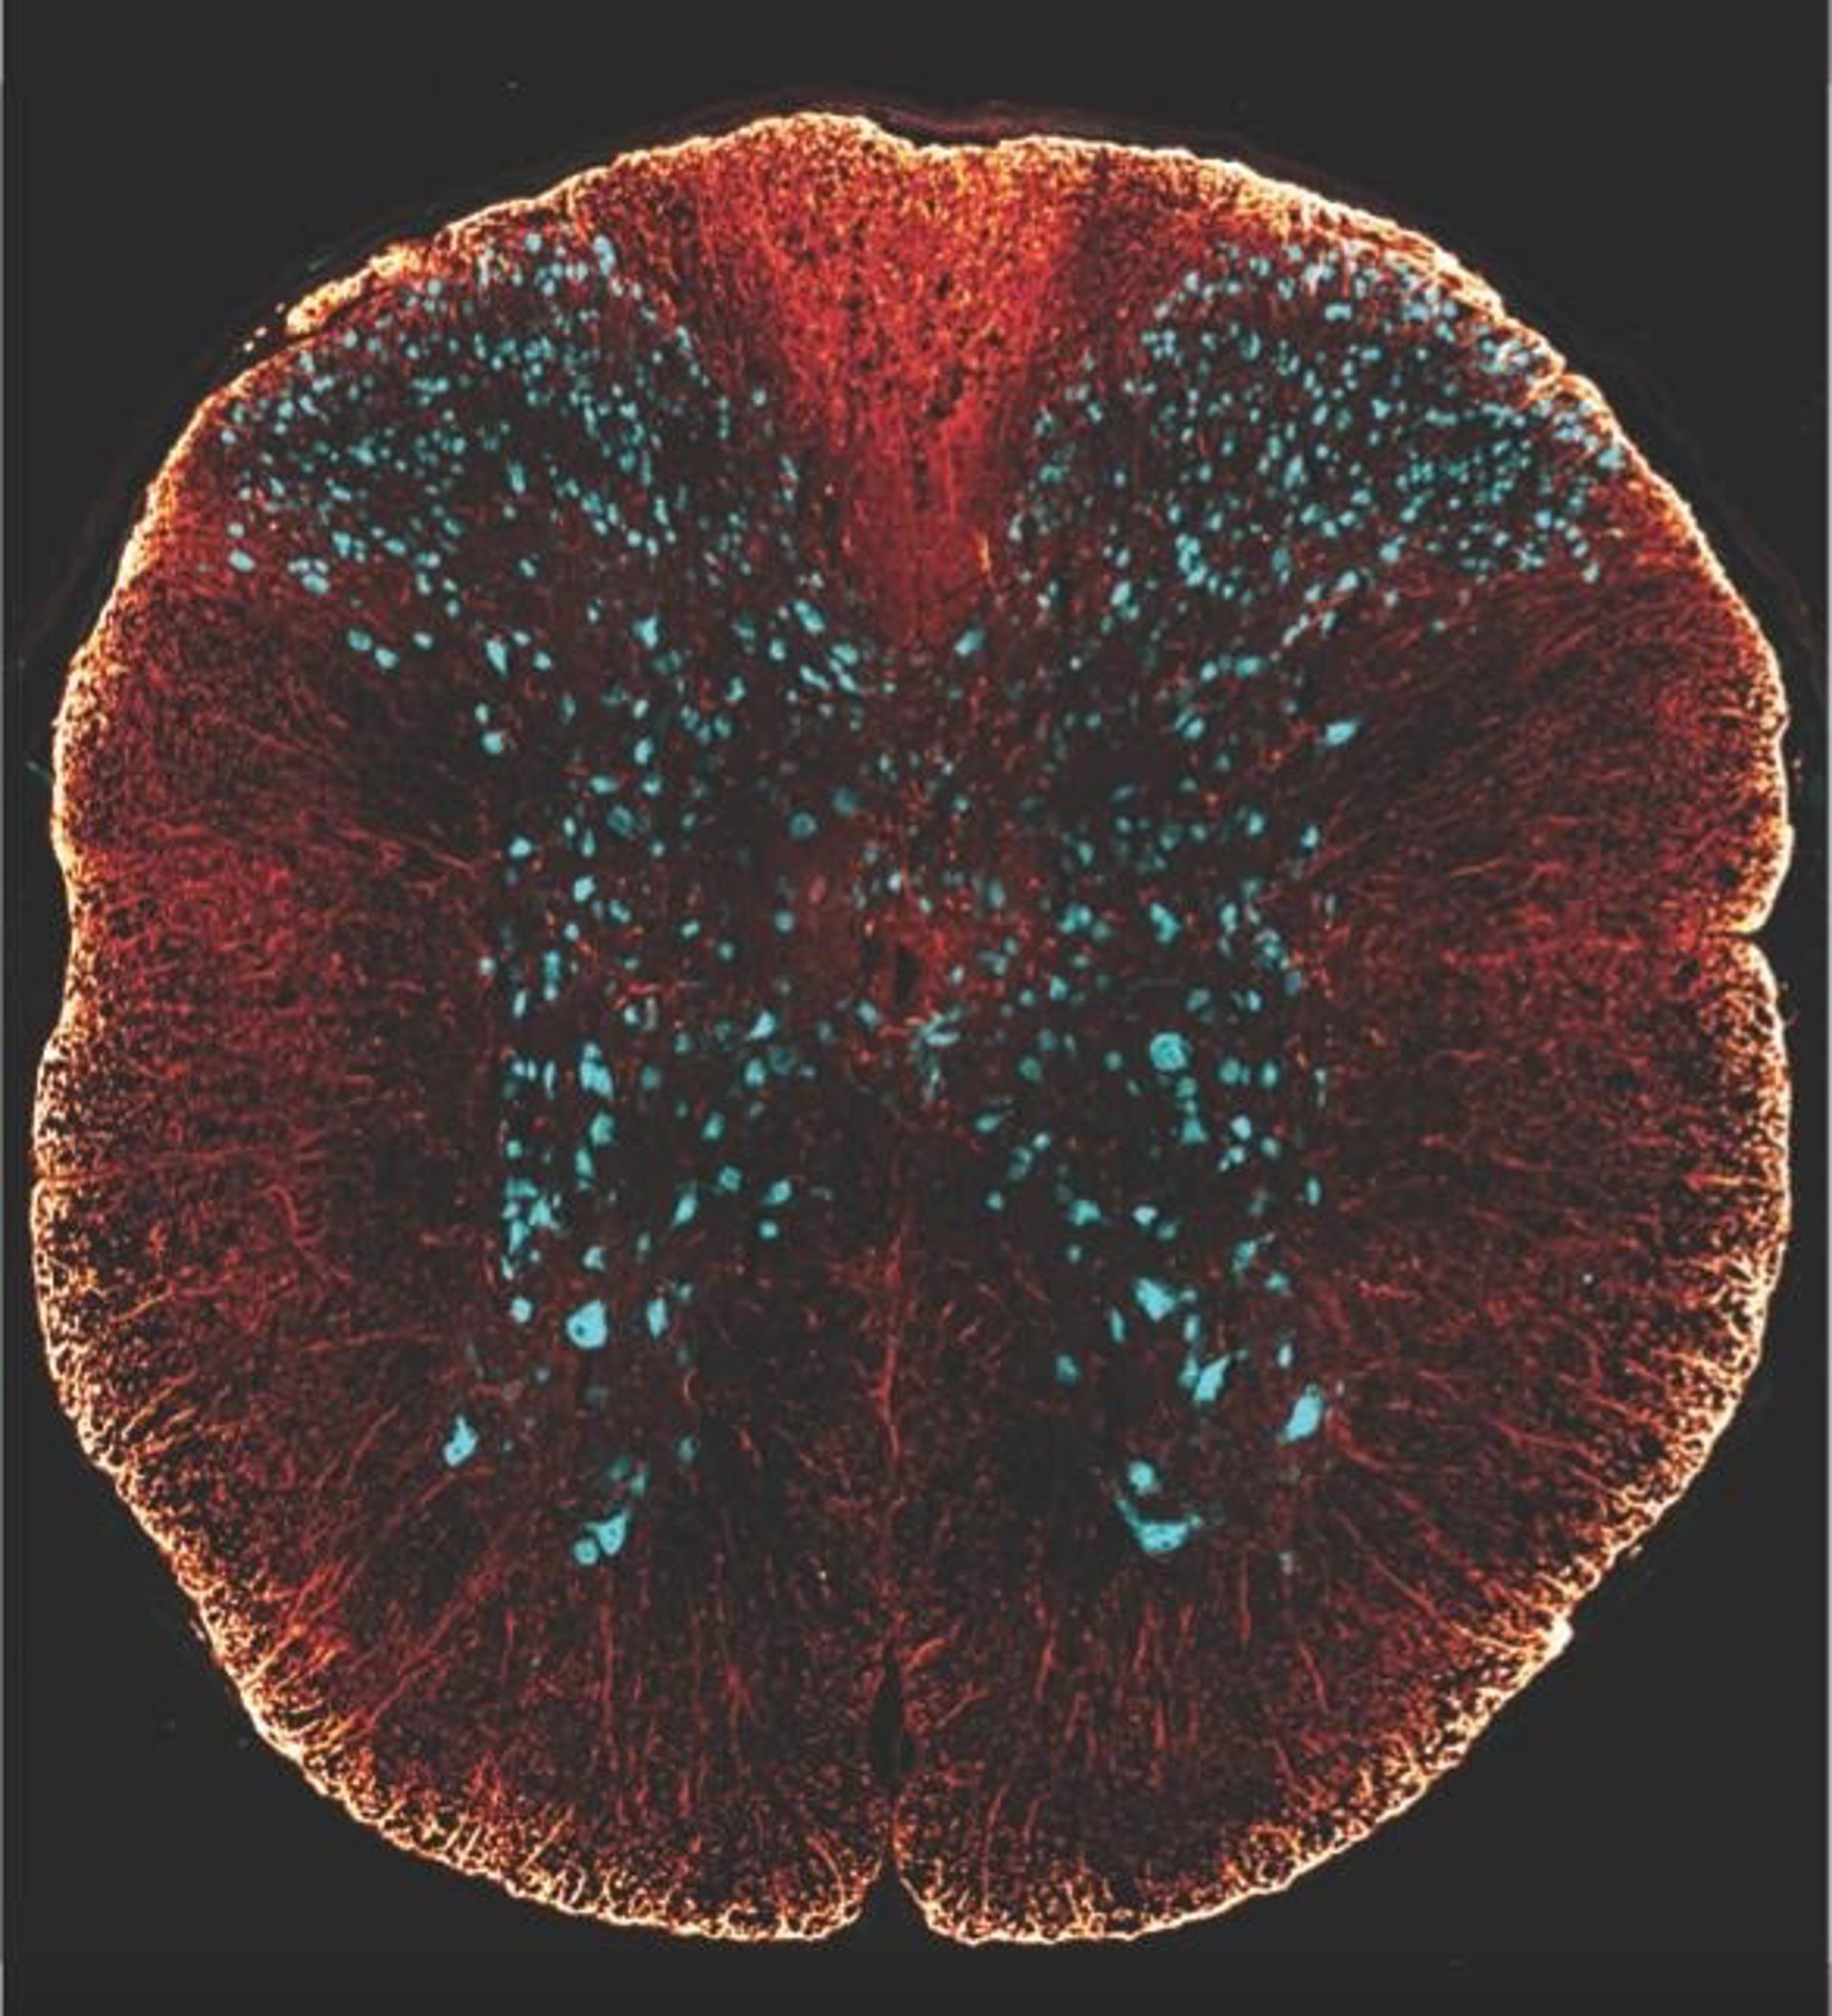

La imagen representa una sección transversal de la médula espinal de un ratón.

La imagen representa una sección transversal de la médula espinal de un ratón. - DIOGO PARAMOS-DE-CARVALHO